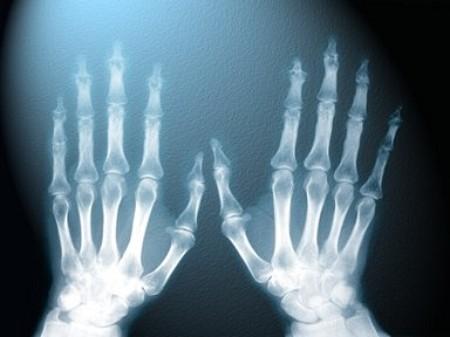

Рентгеновское излучение Это довольно старое открытие, которое было сделано еще в 1895 году, физиком Рентгеном (Wilhelm Conrad R?ntgen). Он совершенно случайно заметил, что излучение катодно-лучевой трубки проходит через довольно твердые предметы (или через части тела), оставляя тень. Причем чем плотнее объект, тем сильнее тень.

Спустя всего несколько месяцев появился снимок руки жены ученого, который является очень известным. В общем, если бы не наблюдательность Рентгена, мы бы не смогли узнавать, что же там случилось с суставом - то ли просто ушиб, то ли перелом, то ли еще что. Хорошее изобретение, очень нужное.